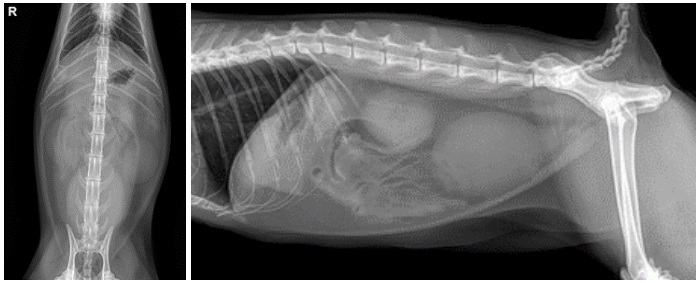

복부 방사선 촬영 결과, 배뇨곤란으로 인해 방광이 많이 확장된 모습이 확인되었습니다. ▼